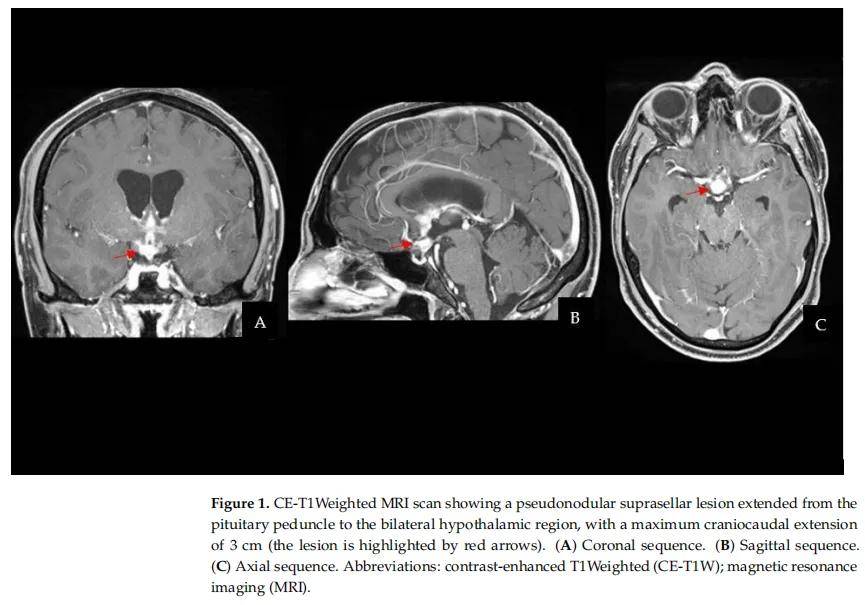

患者男,34 岁,因进行性乏力、食欲减退、广泛肌肉疼痛、多饮及多尿入院。其既往史显示 18 岁时曾诊断为左侧睾丸生殖细胞肿瘤(GCT)。该睾丸肿瘤在另一家医院诊治,在完成肿瘤分期后接受了左侧睾丸切除术。组织病理学证实为混合性生殖细胞肿瘤,由 95% 胚胎癌、3% 卵黄囊瘤及 2% 未成熟畸胎瘤组成。后续予以辅助化疗。治疗结束后的定期临床及影像学随访评估至今未记录到疾病复发。患者被送至急诊科,行计算机断层扫描(CT)显示鞍上高密度肿块伴早期脑积水。CT扫描后行脑部磁共振成像(MRI)扫描,显示鞍上假结节状病变,在T1和T2加权像上均与灰质等信号,增强扫描后呈不均匀强化。病变从垂体柄延伸至下丘脑区及视束,最大颅尾径为 3 cm。考虑到患者既往睾丸GCT病史,神经影像学表现被认为符合中枢神经系统生殖细胞肿瘤(CNS GCT)(图1)。然而,需排除垂体腺瘤、颅咽管瘤、转移瘤、鞍区淋巴瘤及脑膜瘤。因此,建议住院以行进一步诊断检查。随后用于肿瘤分期的全身计算机断层扫描(CT)未发现其他部位病变。眼科评估诊断为左眼颞侧偏盲。血清和脑脊液(CSF)甲胎蛋白(AFP)、β-人绒毛膜促性腺激素(HCG)及癌胚抗原(CEA)均为阴性。鉴于神经影像学表现、临床特征及血清和脑脊液肿瘤标志物阴性,患者接受了病变手术活检,以获取肿瘤标本用于病理诊断和制定治疗方案。

▲图1 CE-T1加权MRI扫描显示鞍上假结节状病变,从垂体脚延伸至双侧下丘脑区域,最大头尾方向延伸 3 cm(病变以红色箭头标出)